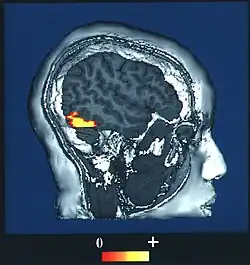

![]() Computer-enhanced fMRI scan of a person who has been asked to look at faces. The image shows increased blood flow in cerebral cortex that recognizes faces (FFA). | |